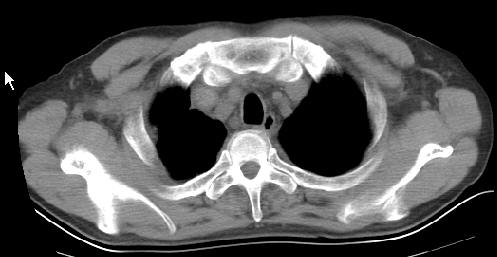

以下是引用草之原在2009-5-2 19:29:00的发言:[br]1.考虑右侧中心型肺ca纵膈淋巴结转移,双侧胸腔积液及右侧叶间裂积液,心包积液。[br]2.两肺上叶病灶,纵膈窗显示部分病灶硬化,考虑:结核。[br][br] [br]

以下是引用ct诊断高手在2009-5-2 19:08:00的发言:[br]我考虑右侧中央型肺癌 伴右肺节段性不张,两肺及纵隔淋巴结转移,右侧胸腔积液。

以下是引用zjzjr在2009-5-2 20:16:00的发言:[br]肺结核,转移瘤.纵隔淋巴结转移或淋巴瘤,右侧包裹性积液、斜裂积液。心包积液。